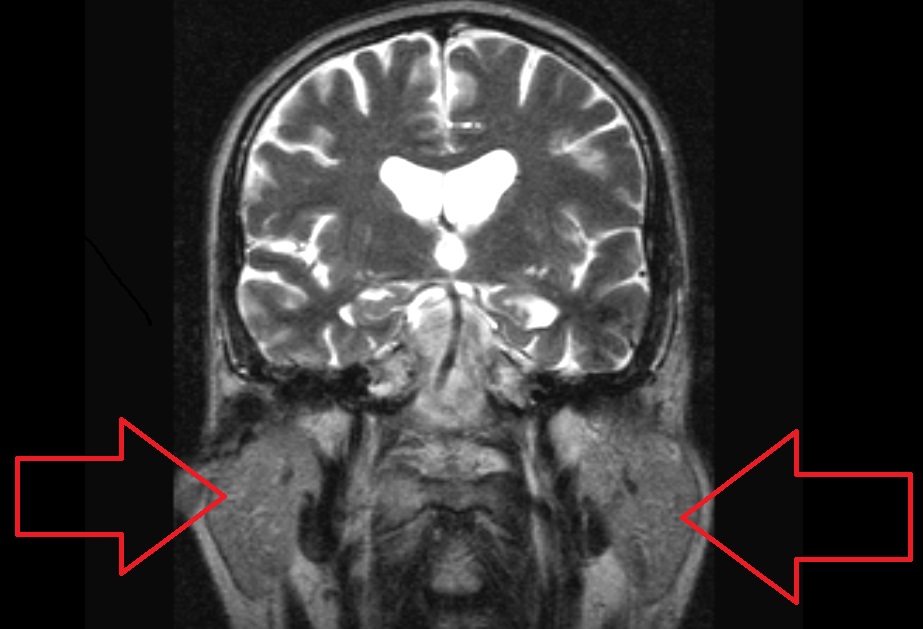

Выраженное воспаление и припухлость слюнных желез у мужчины провоцировало головную боль в области лба и глаз, жжение и зуд в глазах. Болезнь Шегрена не была подтверждена. Улучшение наступило после лечения воспалительного процесса слюнных желез. На МР-томограмах видны увеличенные слюнные железы.